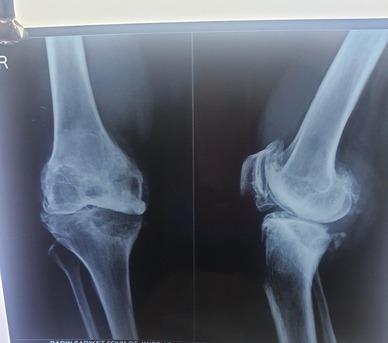

It depends on what kind of fracture you have and where it is. If you have a hairline Fracture or a stress Fracture you might just need to rest and not move that part of your body. If you have a stable Fracture, you might need a cast or a splint. If you have a Fracture, you might need someone to move the bone back into place and then you need a cast. If you have a compound or complex Fracture you might need surgery to fix it with plates or rods or screws. A Fracture treatment doctor in Kolkata will look at your x-rays and tell you what to do.